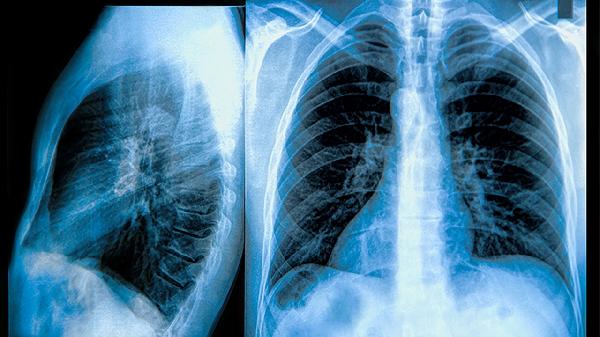

尘肺病属于职业性肺病,病理特征为肺组织不可逆纤维结节形成,早期可能仅表现为咳嗽、咳痰,随着病情进展会出现胸闷气促、肺功能持续下降,严重者可合并肺心病。影像学可见特征性小结节或大块纤维化阴影。慢阻肺的核心病变是小气道炎症和肺泡结构破坏,典型症状为持续性气流受限,表现为活动后呼吸困难反复加重,常伴有慢性支气管炎或肺气肿体征,肺功能检查显示阻塞性通气障碍。